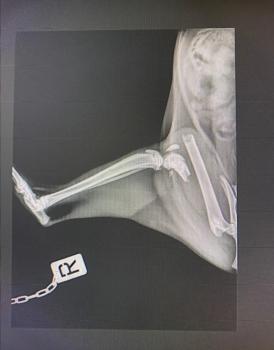

Update 11.04.2026

Bei Dulcinea wurde leider ein Oberschenkelbruch diagnosiert. Die Tierschützer sammeln aktuell Spenden, damit sie bald operiert werden kann.

Sie wurde wahrscheinlich bereits in diesem Zustand ausgesetzt.